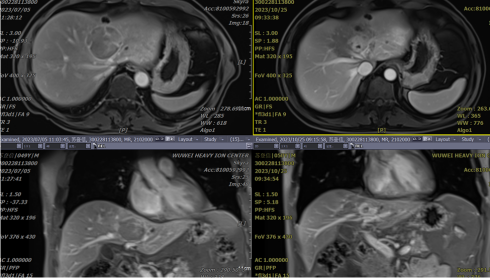

【病例三】患者吴某,女,艺术家,67岁。2022年6月发现肝占位,2022年7月在海南省肿瘤医院行钇90治疗(治疗费用40多万元)。钇90治疗后3个月发现肿瘤未控制,2023年2月21日就诊于中国医科大学附属医院,行超声引导下肝穿刺,病检提示:(肝)符合肝内胆管癌,Ki-67(70%+)。基因检测:未见有临床意义的突变。PD-L1检测:TPS<1%,CPS=1。2023年2月23日行肝动脉栓塞化疗(氟尿嘧啶、洛铂)。2023年4月就诊于武威重离子中心,行腹部彩超:肝右叶可见59×41mm低回声肿物,肿瘤包绕肝内胆管。PET-CT提示:肝胆管细胞癌行钇90治疗后,现肝SIV段不规则稍低密度肿块,其内致密小结节,边缘代谢不均匀环形增高,多考虑肿瘤进展。腹部MR:肝左右叶交界跨肝裂生长边缘强化肿块,6.0×3.6cm,中心强化不明显,周围呈环形强化。武威肿瘤医院重离子中心经MDT会诊,评估具有重(碳)离子治疗适应症,于2023年4月17日行重(碳)离子治疗,并行HFOV脏器运动管理下肿瘤推量,同时行肝门区域淋巴引流区重(碳)离子治疗。患者出院后出现1级放射性皮肤反应,未见其他放射性反应。治疗后3个月(2023年7月),患者在当地体检时复查腹部彩超提示:脂肪肝,未见肿瘤性疾病。后就诊于沈阳市第四人民医院,行腹部彩超亦未提示任何肿瘤性病变。2023年8月于我院行腹部MR提示:见重(碳)离子治疗后改变,肿瘤标记物恢复正常。其他指标保持正常。

wuwei

上图为2025年11月我院复查影像,肿瘤完全消失。

该患者肝脏胆管细胞癌,钇90治疗(费用40多万元)后控制不佳,重离子无创治疗后疗效满意,该患者肝脏胆管细胞癌,钇90治疗(40万)后控制不佳,重离子无创治疗后疗效满意,截止发稿日,重(碳)离子治疗后30个月患者肿瘤完全消失,体力状况良好,生活完全正常。

【病例四】晚期无法接受药物及肝移植的患者,我们先行精准处理左门脉支内的癌栓,保护左肝叶,待左肝叶增大后,再行重(碳)离子治疗处理巨大的肝右叶多个肿瘤。患者肝功转危为安,生活质量恢复正常,生命得到有效且高质量的延续。

【病例五】男性,49岁,肝门部肝细胞癌。我们利用武威重离子特有的HFOV技术解决呼吸动度问题,精准处理了夹在门脉和胆管中央的肿瘤,治疗后肿瘤迅速消失。

左侧为2023年7月重(碳)离子治疗前,右图为重(碳)离子治疗后。重(碳)离子治疗后肿瘤迅速消失,见纤维组织,治疗中患者无任何不适,肝功能始终保持正常。截止发稿日,重(碳)离子治疗后26个月,患者肿瘤完全消失,体力状况良好,生活完全正常。